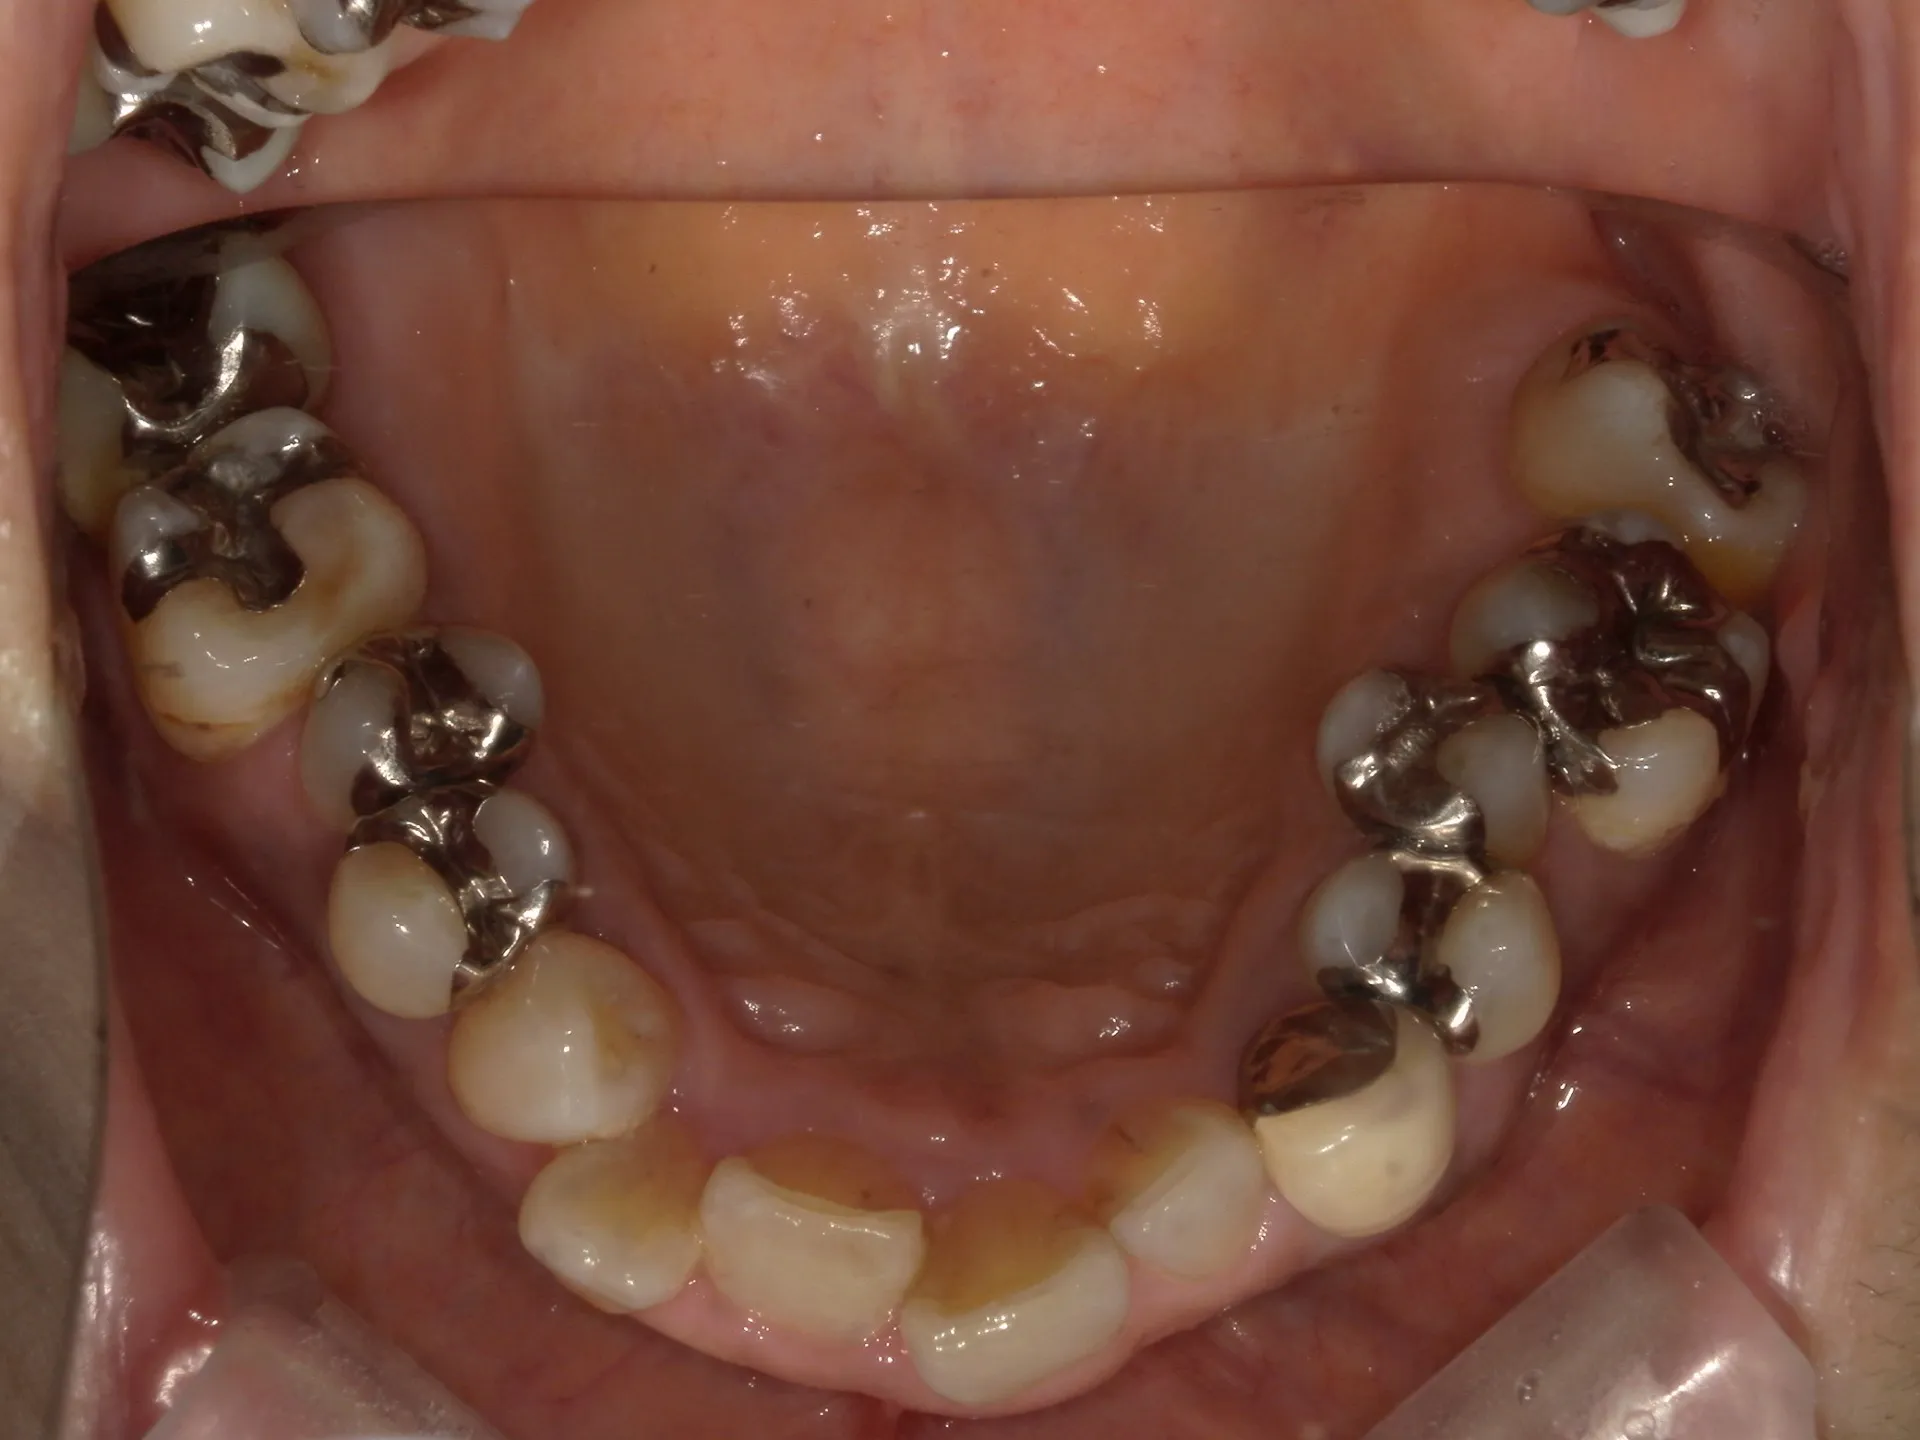

今回は65歳以上でも矯正治療を開始した症例についてご紹介いたします。

しかし、年齢がたとえ定年を迎えたあとであっても十分に矯正が行えて、今後の歯磨きが容易になり、虫歯や歯周病のリスクが減らせて歯を残すことが出来たり、歯並びが良くなったことでモチベーションも上がるなどの矯正後のメリットも非常に高いため、健康的な生活を行う上でも矯正治療は行うことをお勧めします。